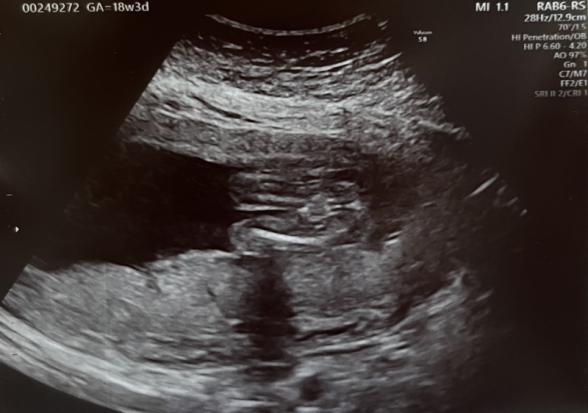

赤ちゃんの性別について教えていただきたいです。

先生からは割れ目のような物が見えるような気がして、女の子寄りかな〜?と言われました。

それとお股の先の白色の部分は何でしょうか?

足を閉じていることもありますので、はっきりと性別がどうかは、わかりにくいように思いました。

お股の先の白いものは、こちらでもあまりよくわかりませんでした。

足の太ももの内側に当たる線にもなるのかな、皮膚同士の重なりの部分になるのかなと思いました。